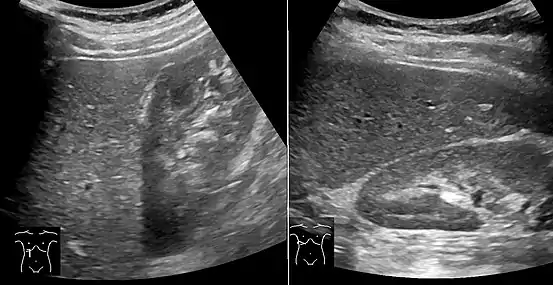

On abdominal ultrasonography, steatosis is seen as a hyperechoic liver as compared to the normal kidney.

Abdominal ultrasonography with the liver and kidney side by side (left image) may give a false impression of hyperechogenic liver, so it's preferably done with the organ borders facing the ultrasound probe (right image, of the same case).